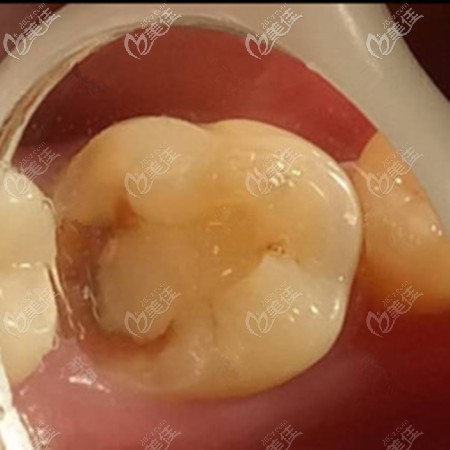

术前照片:

你可以看一下填充后的颜色尤其的逼真,主要是色泽还比较好,不会特别的呆板,一看就是假的。